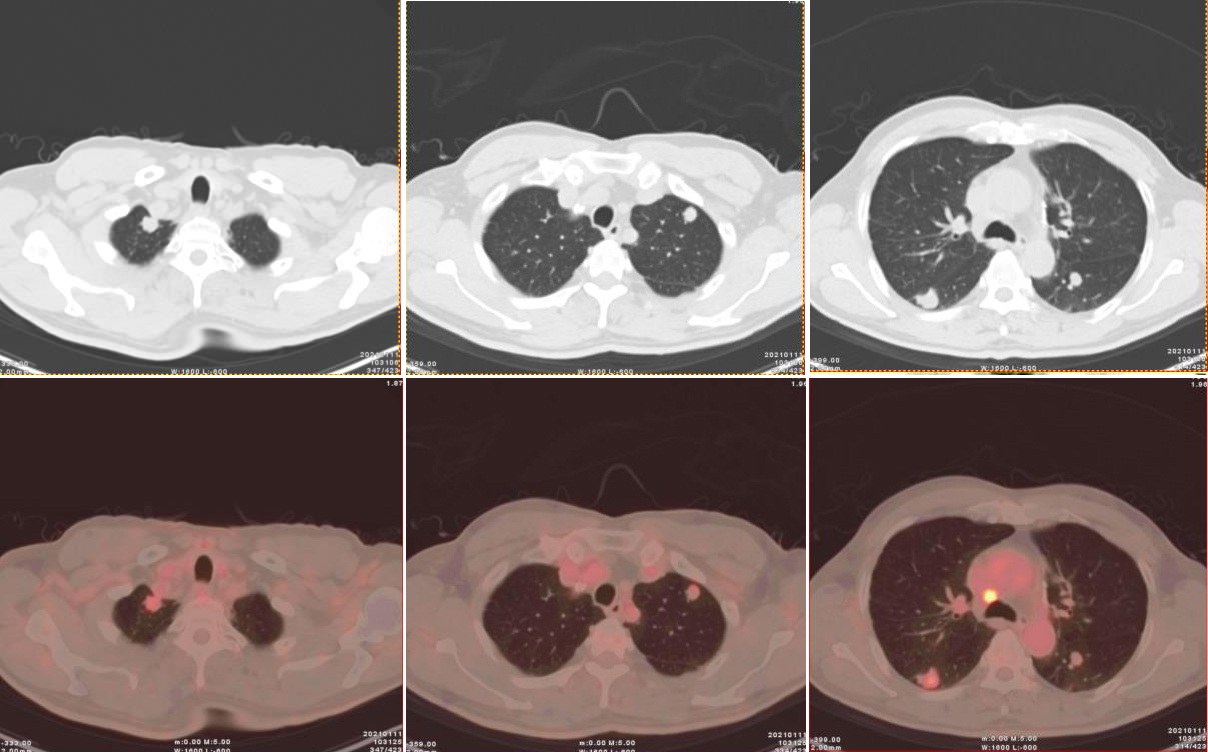

圖2、3:(上為CT橫斷位圖像,下為橫斷位融合圖像):雙肺多發(fā)結(jié)節(jié),部分可見(jiàn)淺分葉,邊緣可見(jiàn)段毛刺,代謝輕度增高。

雙肺見(jiàn)多發(fā)散在大小不一實(shí)性結(jié)節(jié),邊界尚清,形態(tài)不規(guī)則,部分邊緣見(jiàn)短棘突及淺分葉,密度不等,CT 值約19~30Hu,大者位于右肺下葉背段,大小約 1.7×1.8×2.1cm;部分病灶放射性攝取輕度增高,早期 SUVmax 3.47,1小時(shí)延時(shí)顯像示病灶放射性攝取有所減低,SUVmax 2.1。

影象:雙肺散在多發(fā)結(jié)節(jié),部分代謝輕度增高,考慮多中心原發(fā)肺癌可能性大。

PACC為低度惡性腫瘤,較常見(jiàn)的肺癌 (如鱗狀細(xì)胞癌)預(yù)后好,但在CT上,PACC無(wú)明顯特異性表現(xiàn),與常見(jiàn)的肺癌類(lèi)型無(wú)法鑒別。本例中雙肺十幾個(gè)結(jié)節(jié)中部分病灶呈現(xiàn)放射性攝取輕度增高,早期SUVmax 3.47,1小時(shí)延時(shí)顯像示病灶放射性攝取有所減低,SUVmax 2.1,與其低度惡性的病理類(lèi)型一致。

此例為雙肺多發(fā)腺樣囊性癌,更屬罕見(jiàn),診斷難度極大。通過(guò)耐心分析每一個(gè)結(jié)節(jié)的特點(diǎn),發(fā)現(xiàn)其都呈現(xiàn)略有分葉毛刺的形態(tài),不似轉(zhuǎn)移瘤常見(jiàn)的類(lèi)圓形、邊緣光滑的結(jié)節(jié);全身PET/CT未見(jiàn)其他組織器官的占位性病變或高代謝灶,因此不考慮雙肺轉(zhuǎn)移瘤;此外,雙肺多發(fā)結(jié)節(jié)邊緣無(wú)炎性病變的滲出性改變,亦未見(jiàn)結(jié)核常見(jiàn)的鈣化及衛(wèi)星造,代謝上沒(méi)有肺淋巴瘤常見(jiàn)的顯著增高。